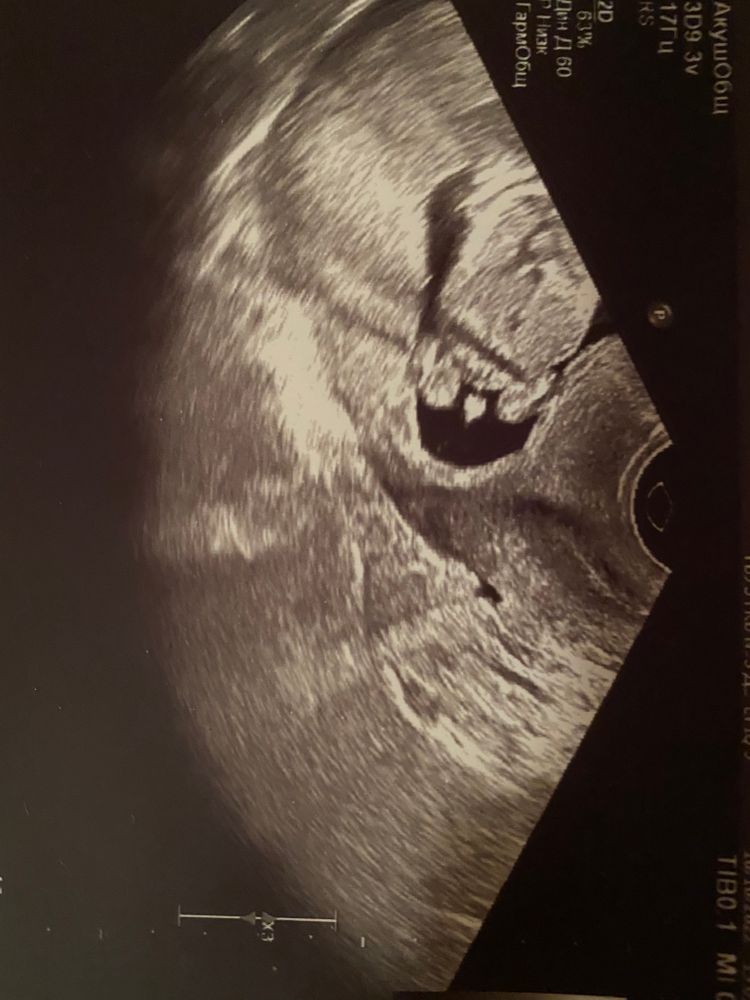

Как думаете - мальчик?

Слушайте, даже я вижу не пуповину)

Мальчик ))

Если б это была часть пуповины, то было бы видно девочку.

Это 100% мальчик 😊